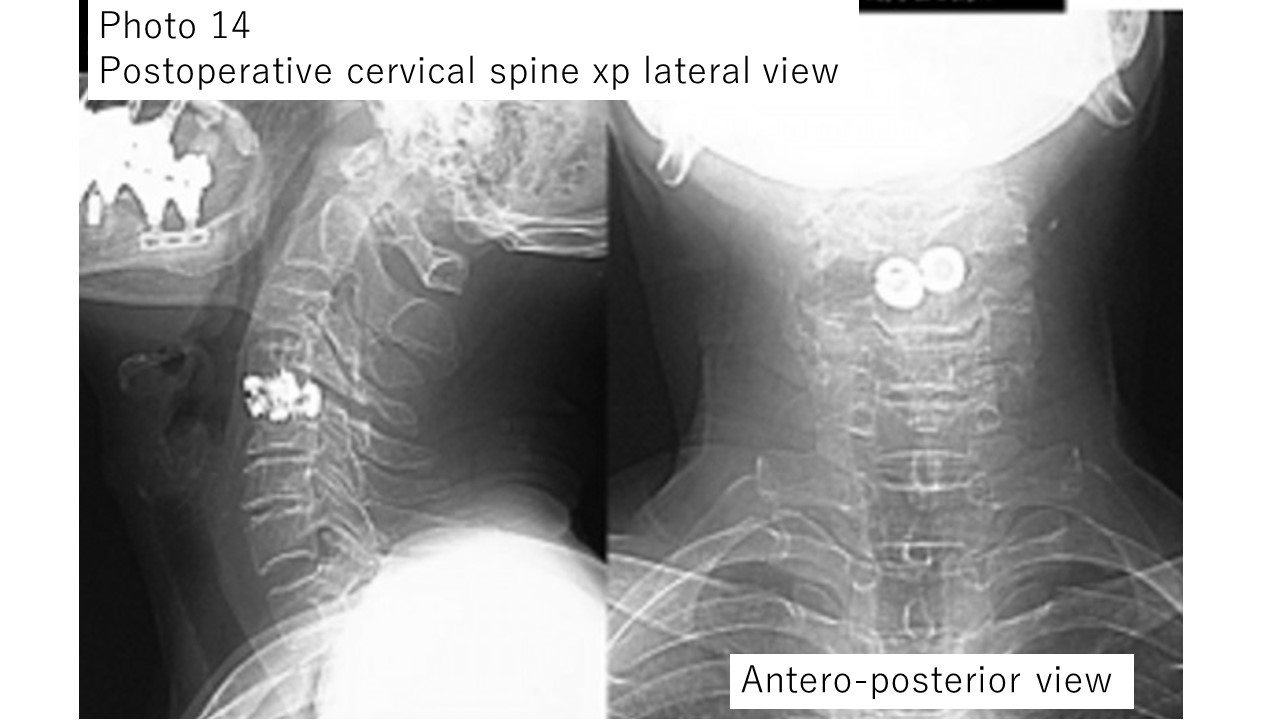

The patient became ambulatory early after surgery and was discharged home 2 weeks after surgery.Photo 14: Plain X-ray image of the cervical spine after surgery for the patient in Photo 13.

Photo 13: Due to cervical disc herniation, there was gait disturbance and numbness in the fingers, and cervical spine anterior fusion surgery (using a titanium cage) was performed.

Postoperative cervical spine CT examination showed that the spinal cord was not compressed in the operated area.

The patient's preoperative symptoms improved and he was discharged home. This surgery is a relatively new technique in which a titanium screw is inserted in place of the removed intervertebral disc to fix it.